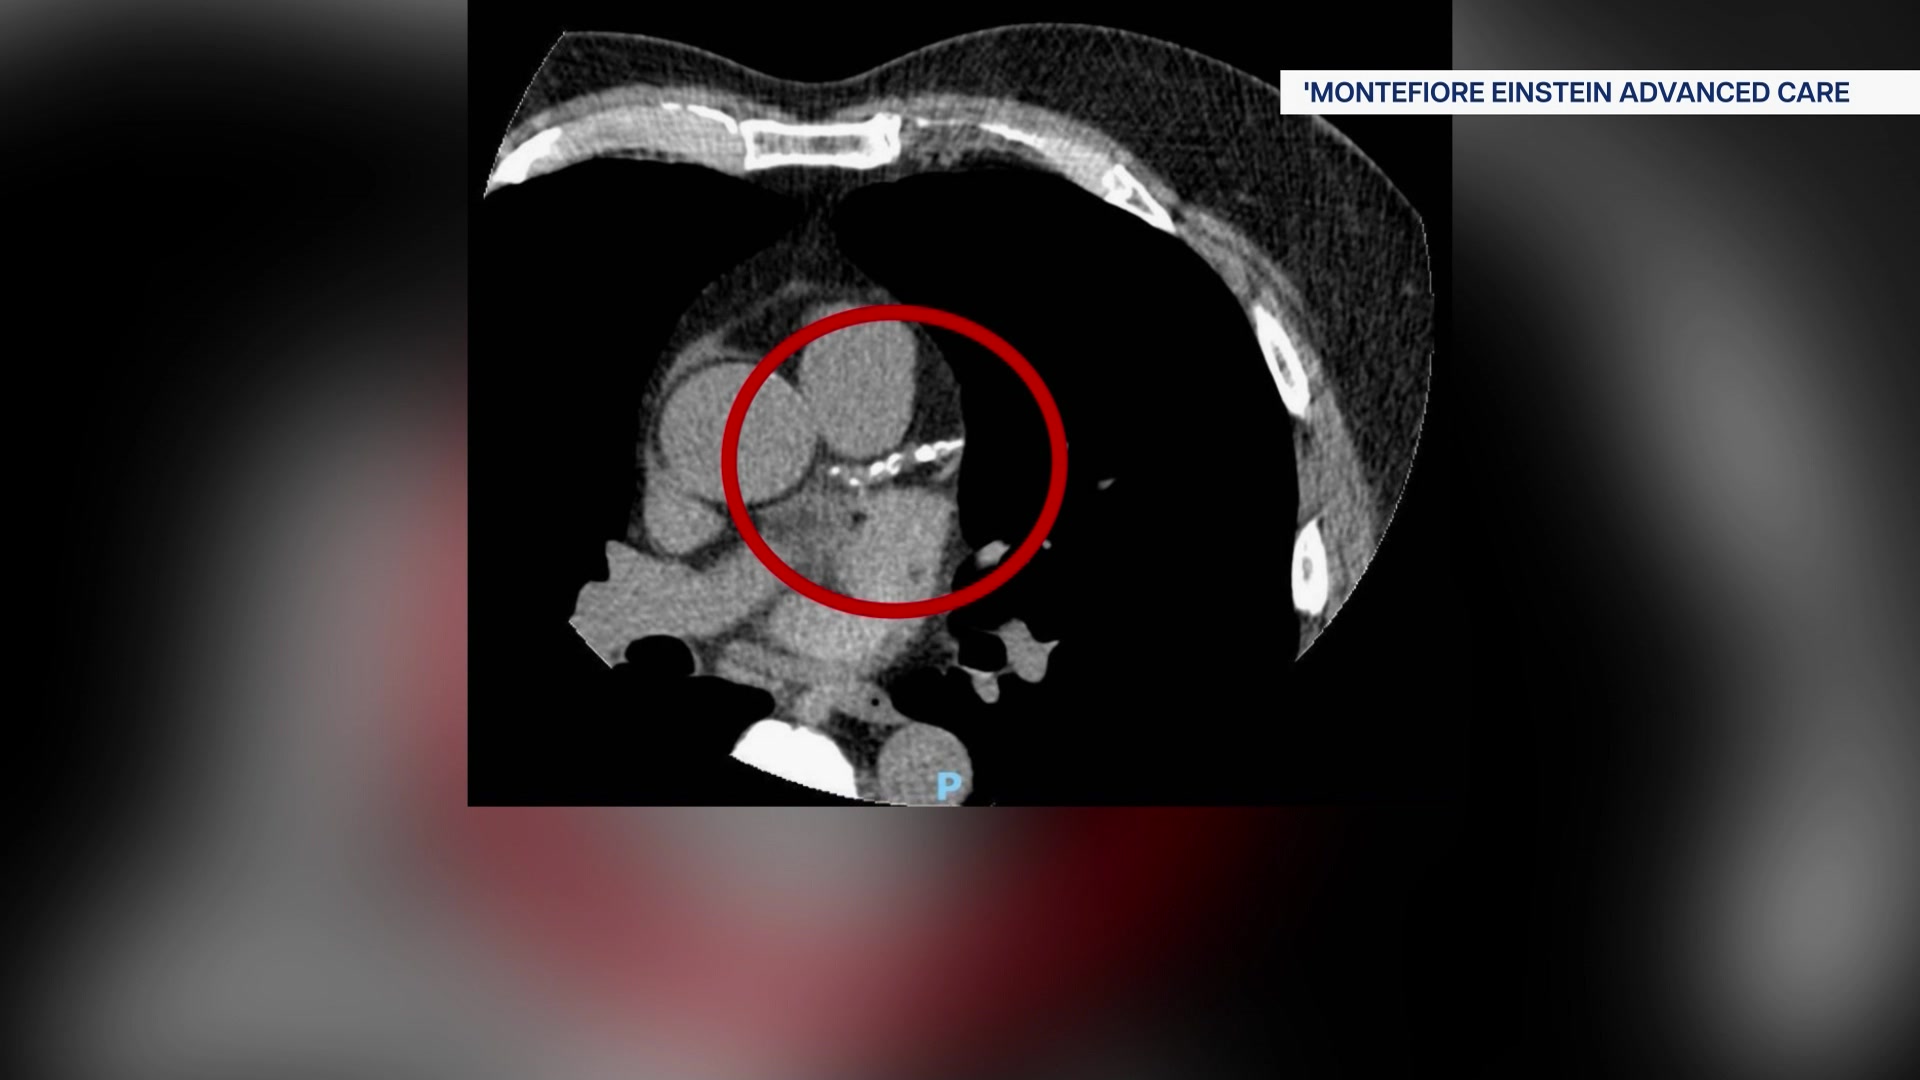

472026CTheart_2026-04-07-05-22-49

Updated heart disease guidelines aim to prevent cardiac events before they happen